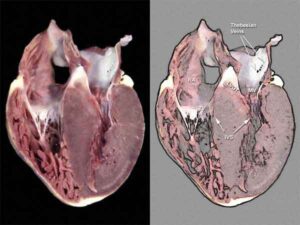

Cardiomiopatia da stress: subdola e più diffusa del previsto La risonanza magnetica mostra una sofferenza cardiaca anche in assenza di...